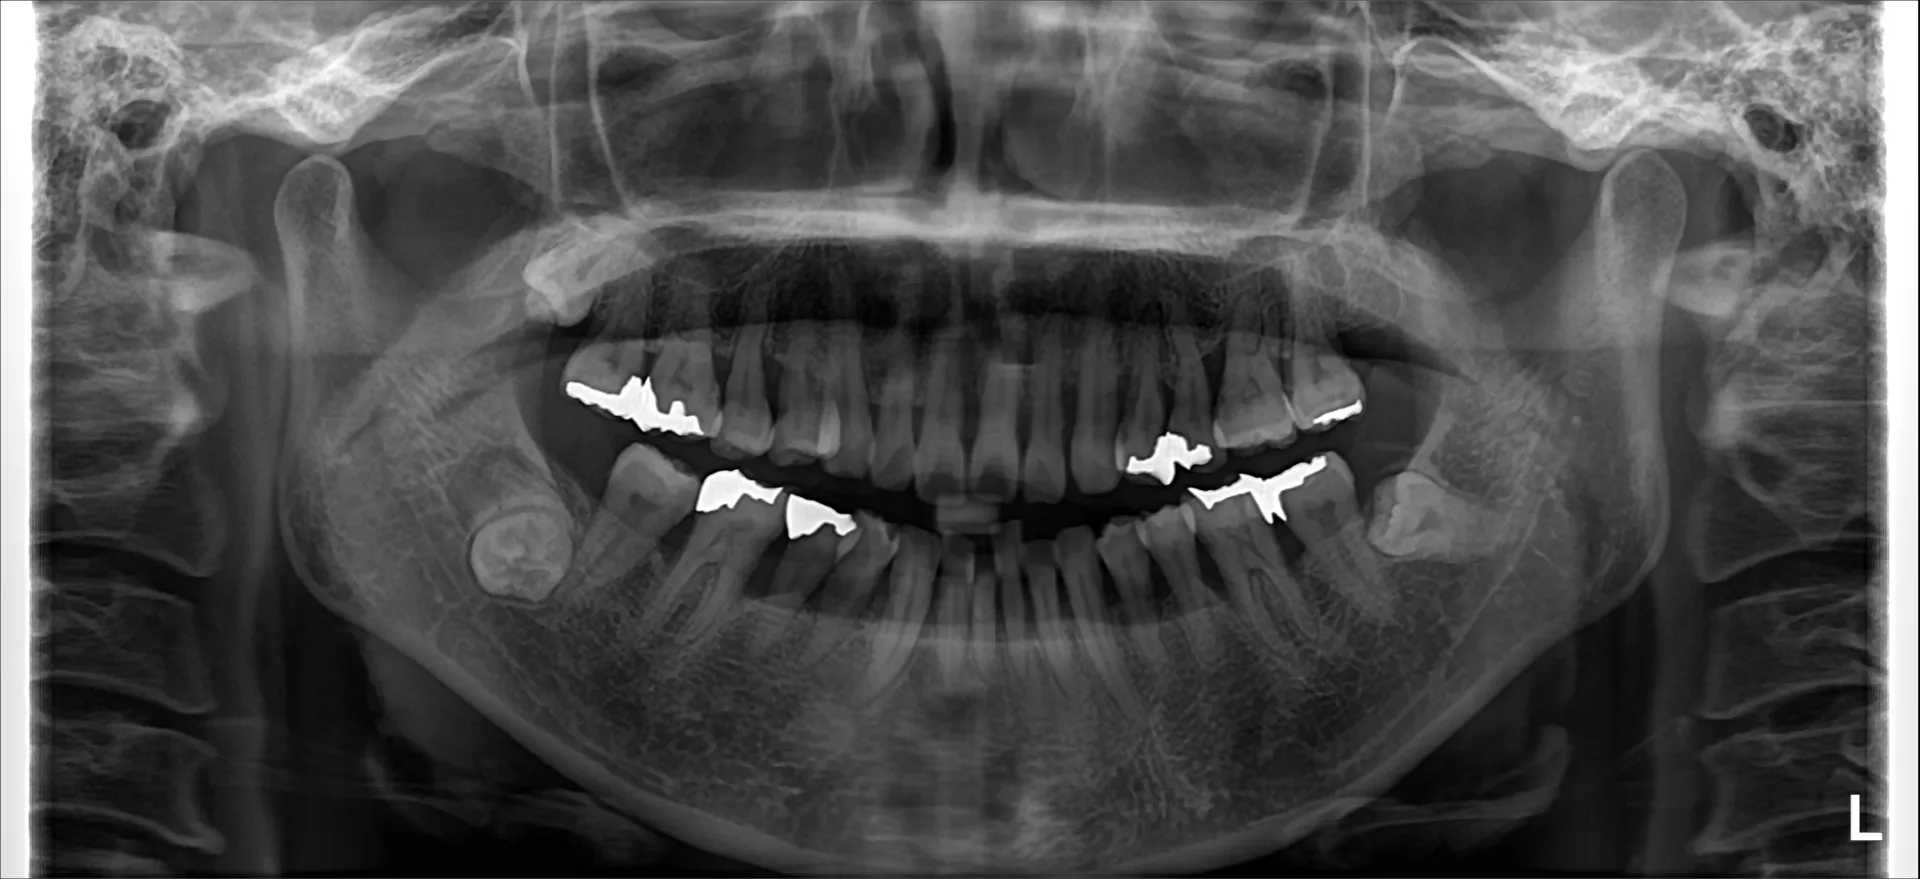

当院では矯正治療と歯周治療を平行して行うことにより矯正治療を進めていけることができました。

しかしながら、今回の治療途中で歯茎が腫れるなどの影響もあり、歯周治療中の矯正治療はリスクであることは患者様にも初回の段階で説明していることもあり、患者様もこの状態の歯並びで満足しており、歯を残すためにも今回は矯正治療を中断する希望をされました。